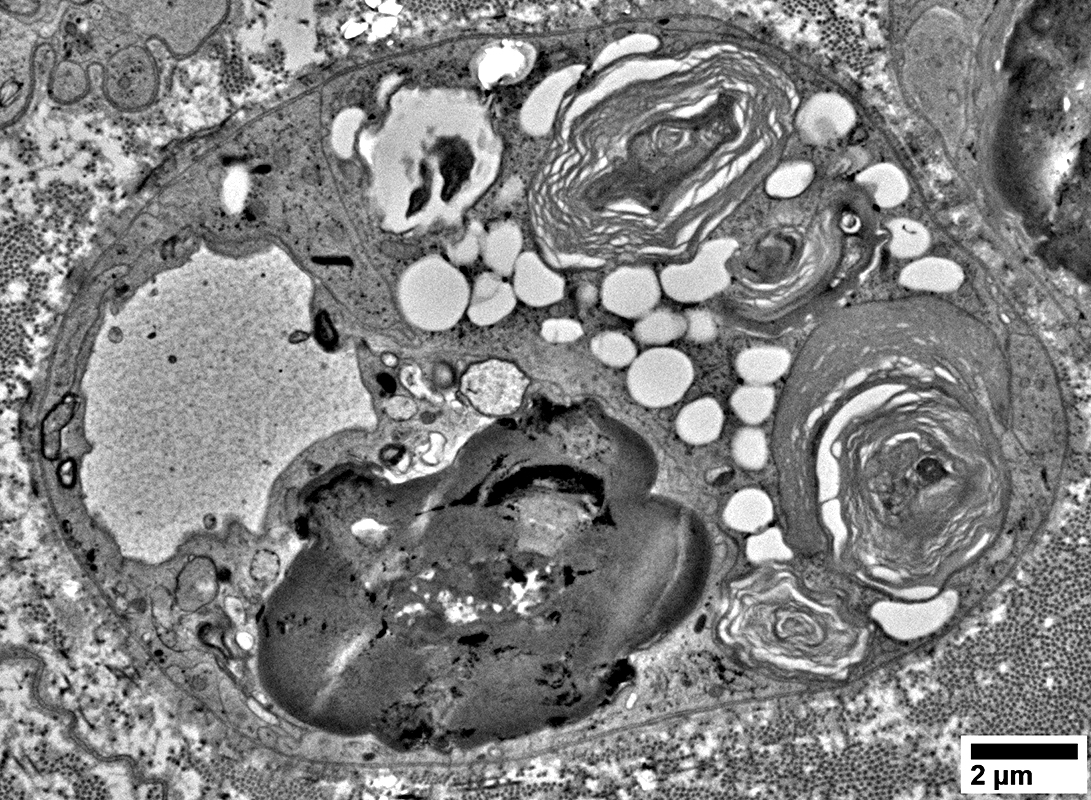

Lipid Droplets & Myelin debris segregated in different Schwann cell processes

From: R Schmidt

Cell Processes: Other